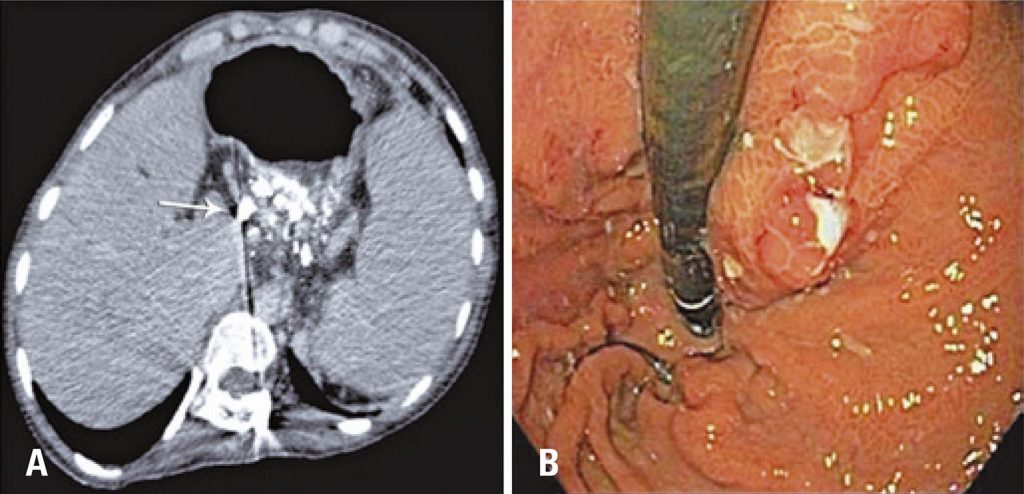

Figura 4

Exames de controle após 30 dias. (A) Tomografia computadorizada após 30 dias mostra varizes gástricas preenchidas pelo agente líquido (Onix®), seta branca. (B) Endoscopia digestiva alta de controle após 30 dias do procedimento